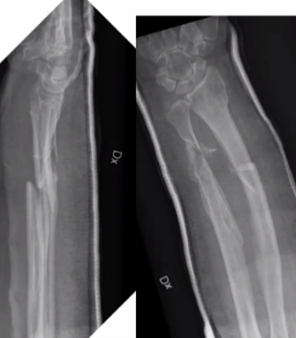

Q

65-årig kvinna

• Rökare, möjlig alkoholöverkonsumtion

• Tidigare kons beh distal radiusfraktur

• Ramlat över mattkant

• Sluten skada. NV intakt

Vad göra?

A

Plattan bra för att styra rotationskrafter, men direkt benläkning i radius och callusläkning i ulna